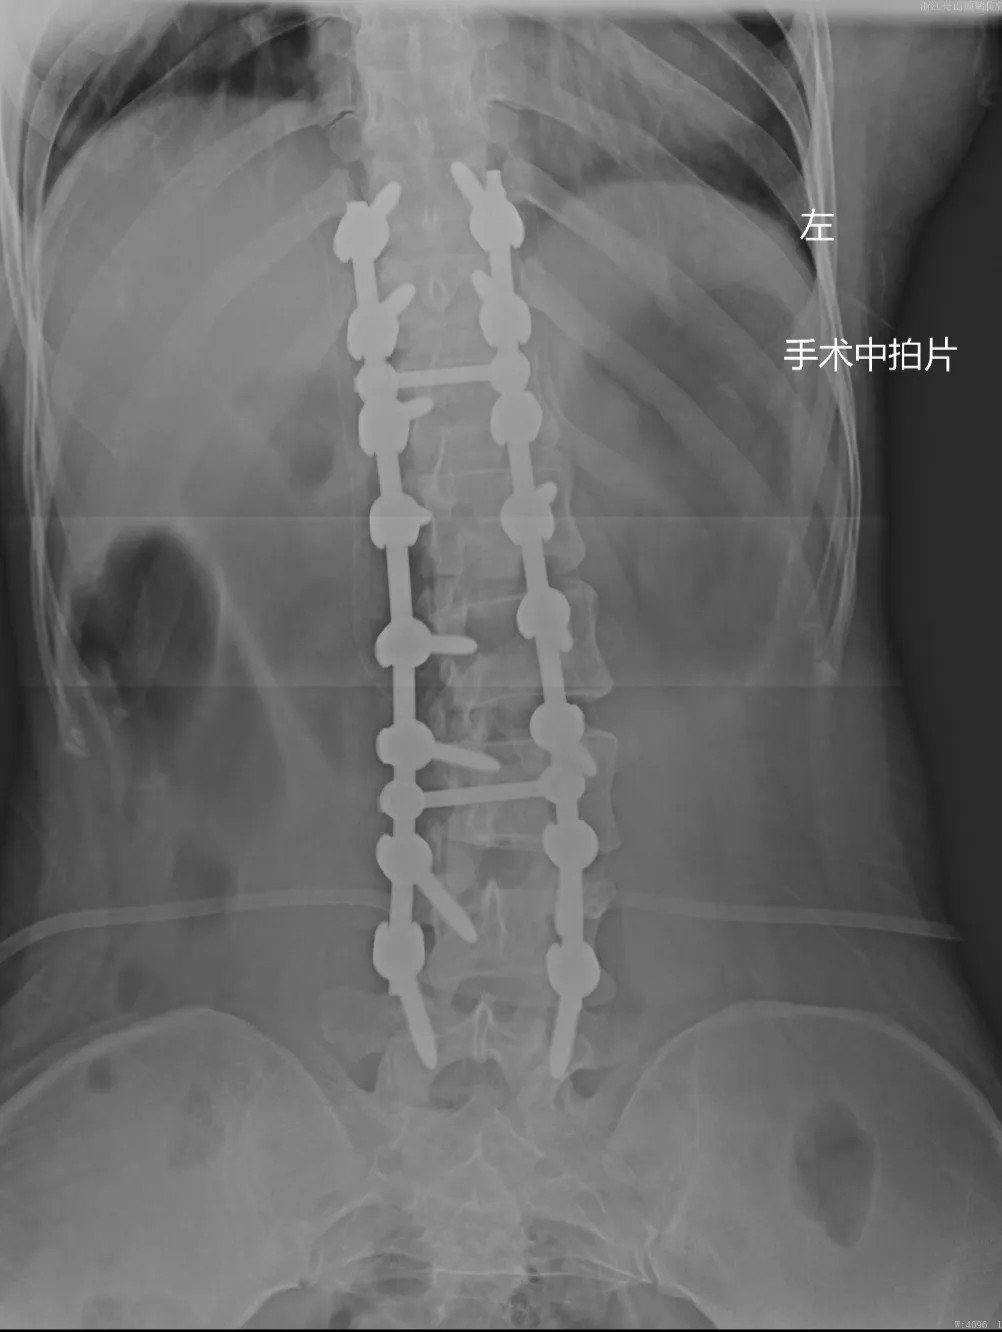

在充分的術(shù)前準(zhǔn)備后,脊柱科、微創(chuàng)治療中心專家團(tuán)隊(duì)為文女士(化名)進(jìn)行了脊柱側(cè)彎矯形、植骨融合內(nèi)固定術(shù),歷經(jīng)近4個(gè)半小時(shí)的精細(xì)操作,手術(shù)圓滿完成。術(shù)中全程使用術(shù)中電生理監(jiān)測(cè)系統(tǒng),每步都力求精準(zhǔn)細(xì)致。

術(shù)后恢復(fù)

術(shù)后,在我院醫(yī)護(hù)團(tuán)隊(duì)的精心護(hù)理下,文女士(化名)恢復(fù)順利,繼續(xù)住院治療幾天后便出院了。

近日,文女士(化名)來院復(fù)診,整體恢復(fù)良好,術(shù)前活動(dòng)不便的癥狀明顯好多了,腰背部肌肉也恢復(fù)了一些,脊柱生理曲度相比術(shù)前有所恢復(fù),側(cè)彎癥狀也明顯改善,下胸椎、腰椎向左側(cè)側(cè)凸畸形較前改善,腰背部轉(zhuǎn)側(cè)活動(dòng)不利較前改善。